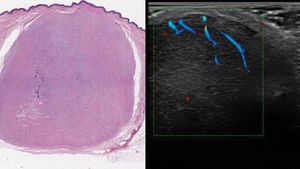

With the clinical diagnosis of either a sclerotic fibroma or a basal cell carcinoma, a cutaneous ultrasound is performed. With 18 and 22MHz probes, a hypoechoic, well-demarcated 13.1mm×19mm×22mm tumor is revealed, located in the dermal plane and subcutaneous cellular tissue. Doppler mode shows increased peripheral vascularization with small vessels of arterial flow characteristics (Fig. 1).

These findings allow us to rule out the presence of basal cell carcinoma, given the absence of hyperechoic punctation on the ultrasound and, in the patient's clinical context, guide diagnosis towards a storiform collagenoma. The ultrasound image is consitent with previous descriptions of storiform collagenoma, adding the increased peripheral vascularization, which is consistent with telangiectasias in the histology and dermoscopy of the lesion.